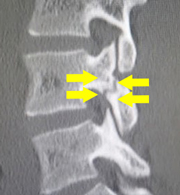

腰部脊柱管狭窄症のMRI画像。神経が複数箇所で狭窄を来している。